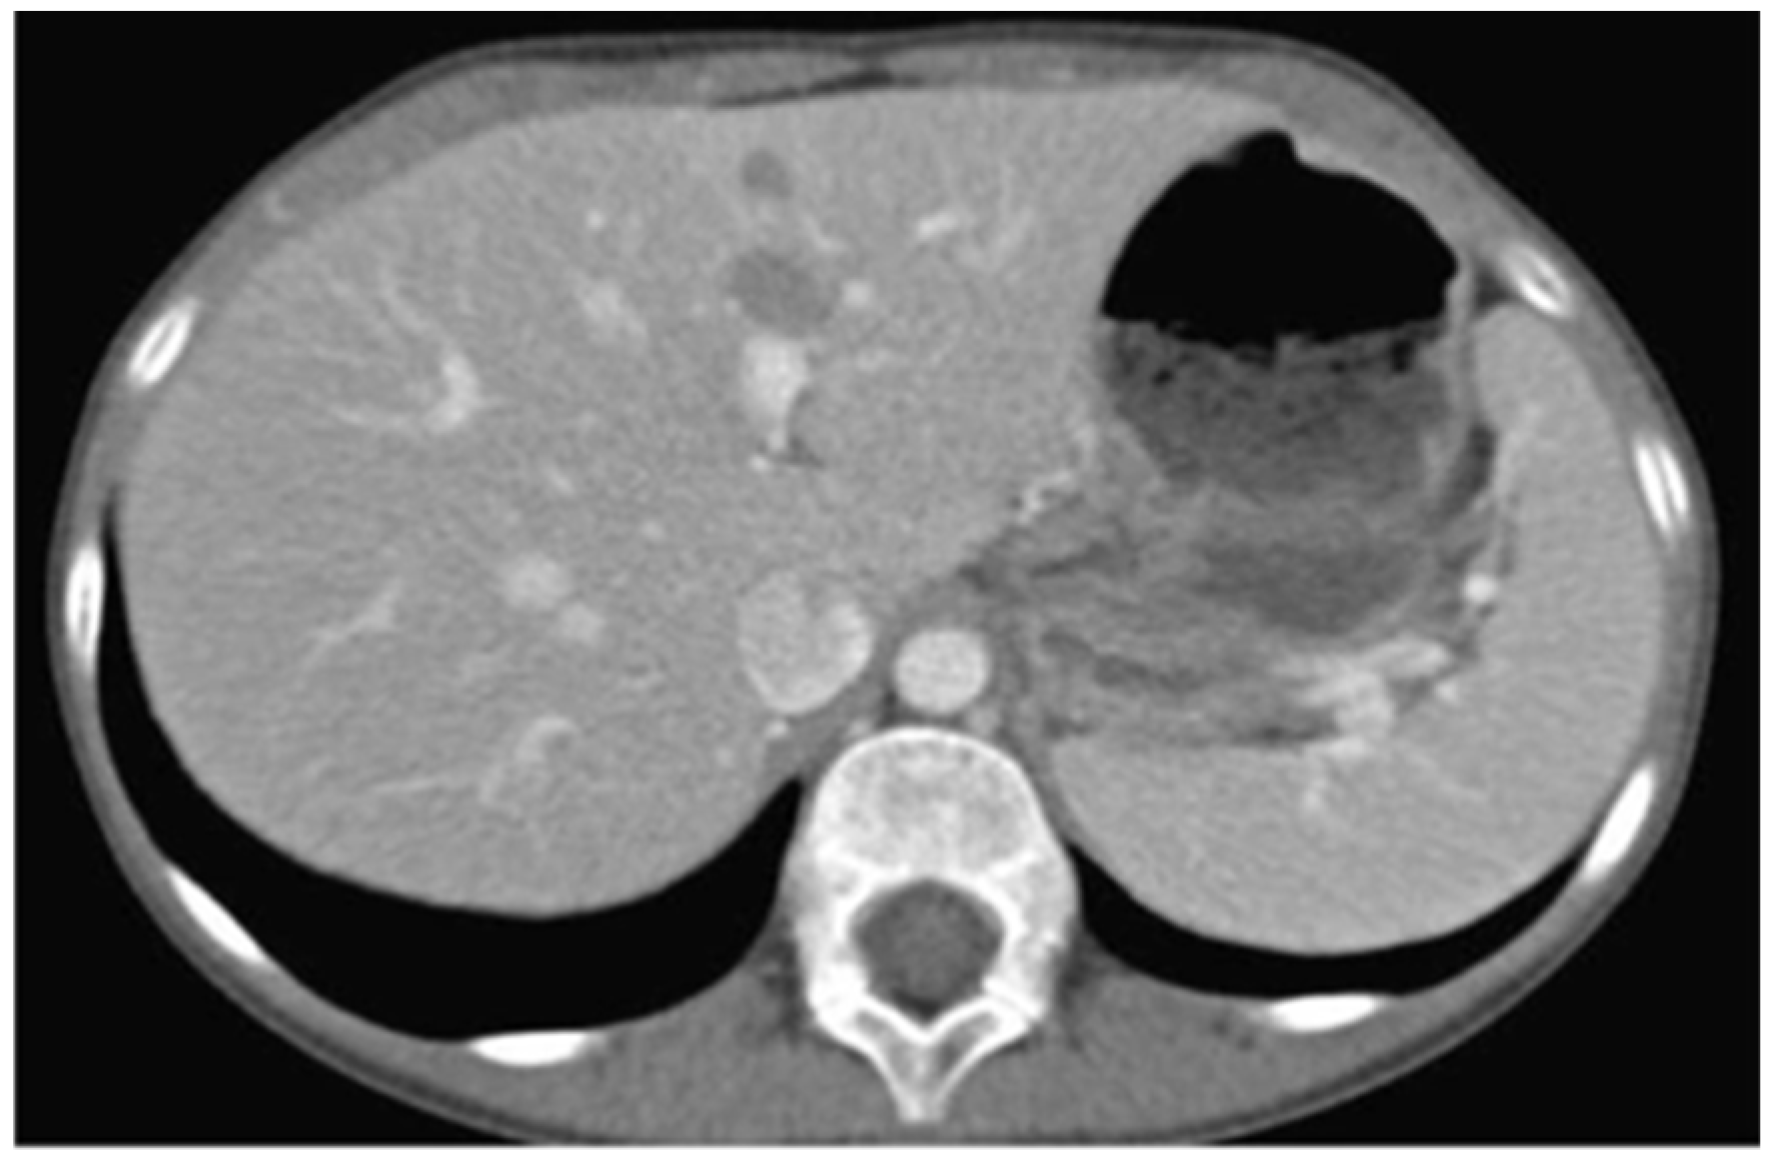

The patient was promptly referred to the Department of Pediatric Oncology of the Children’s Hospital for complete work-up and staging. Full body CT and PET/CT scanning revealed multiple lesions in the skeleton (including the skull, vertebrae, ribs, humerus, femur, and pelvis), liver (Figure 6), and pelvic lymph nodes. Bone marrow aspiration revealed infiltration (15–20%) by neoplastic lymphocytes. The disease was classified as stage IV without CNS involvement.

Figure 6.

Abdominal CT showing diffuse tumor infiltration of the liver.